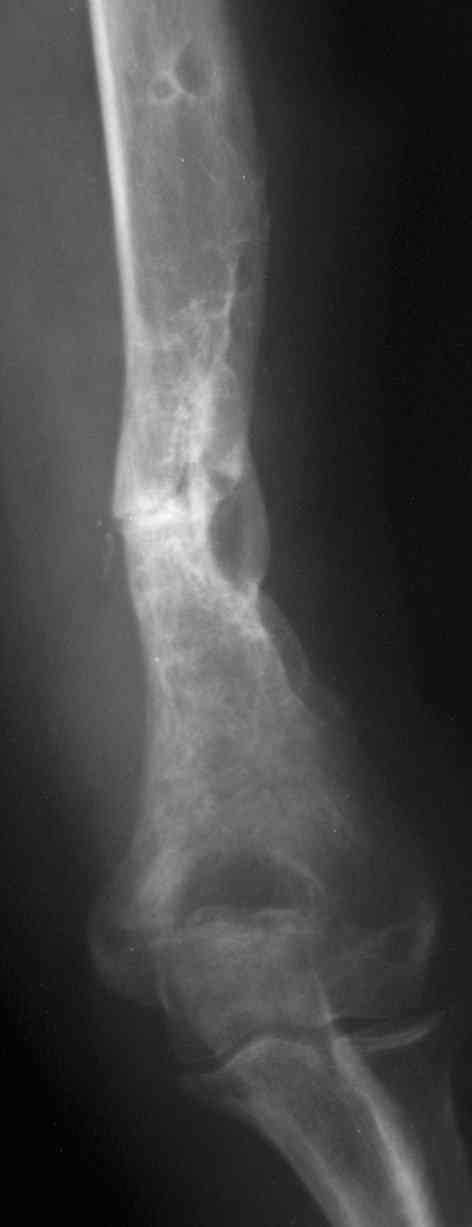

В подобном случае мы бы применили чрескостный остеосинтез. Пример - в приложении.